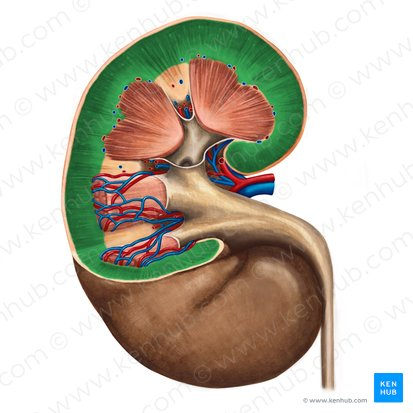

Renal capsule

Surrounds kidney

protection and support

Green

Renal pelvis

Opening for ureter, veins and artery to enter kidney

makes the bean shape of the kidney

Renal cortex function

Formation of urine in kidneys

Erythropoietin production

Green

Renal Medulla

Collect and transport urine

Multipyramidal: Cattle, Swine

Unipyramidal: Feline, Canine

Green

Renal cortex